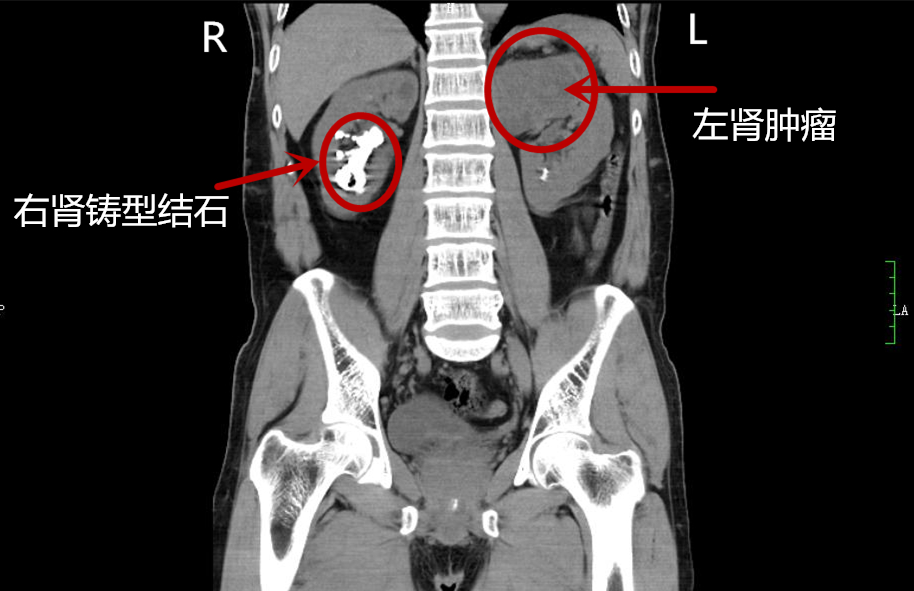

术前泌尿系三维成像提示:右肾铸型结石、尿道结石、左肾占位性病变伴有强化

马王堆院区的泌尿四科就诊。经检查发现,王大爷有尿道结石、双肾多发结石,右肾为铸型结石,左肾占位性病变即左肾肿瘤。无论是左肾的肿瘤,还是右肾的结石,都需要尽快手术,不然将危及生命。